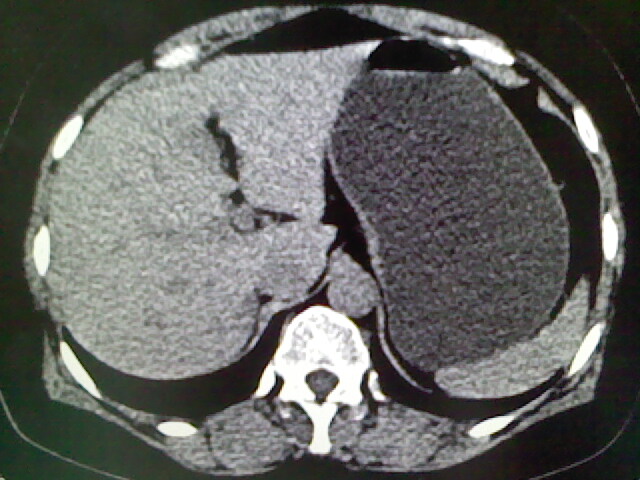

以下是引用卜一在2009-4-2 13:26:00的发言:[br]胆囊颈部结石伴胆囊炎!另:建议增强,待除外肝内占位及胆囊占位!

以下是引用liaoqiang在2009-4-2 16:23:00的发言:[br]胆囊是否切除?胆囊颈区致密影考虑金属夹?结石?肝脏右叶低密度影,考虑增强。